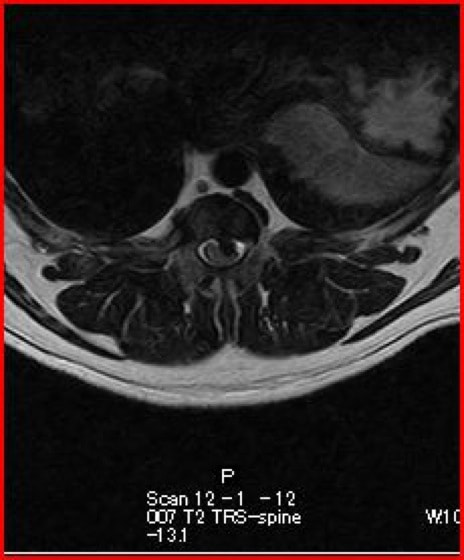

〈MRI検査:胸腰部椎間板ヘルニア2〉

突然ギャンと鳴き両後肢麻痺したとのことで来院されました。触診にて腰部の圧痛を認めました。尿失禁が認められ、深部痛覚は消失していました。聴診上での異常はみられず、後肢の股圧は触知可能でした。血液検査、胸腰椎のレントゲン検査では異常を認めませんでした。MRI検査の結果、第3腰椎領域にてT1強調画像で等信号、T2強調画像で等〜やや高信号、造影剤にて均一に増強される脊髄を腹側から圧迫する腫瘤性病変を認めました。